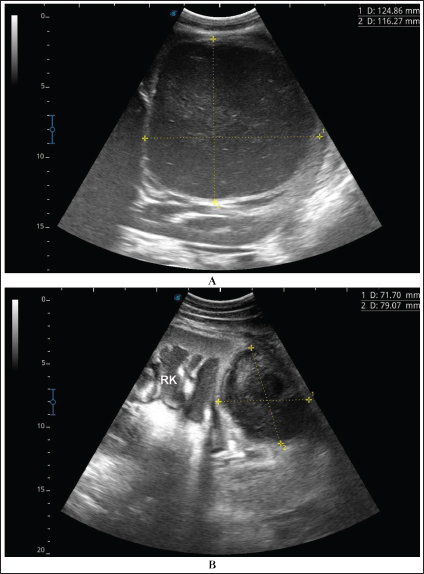

Fig. 4. Ultrasonographic findings of camel number 1 with abscessation of the right kidney. A large abscess was found in image A measuring 12.5 × 11.6 cm with hypoechoic contents and a thick capsule. The abscess in image B compresses the parenchyma of the right kidney (RK) and measuring 7.2 × 7.9 cm with echogenic contents and a thick capsule.

A detailed description of the renal abscesses is presented in Figures 410. Figure 4 shows sonographic findings in camel number 1 with abscessation of the right and left kidneys. A large abscess measuring 12.5 × 11.6 cm with hypoechoic contents and a thick capsule was detected. A second abscess in the same camel was imaged compressing the parenchyma of the right kidney and measuring 7.2 × 7.9 cm with echogenic contents and a thick capsule. Figure 5 shows ultrasonographic results in camel numbers 2 and 4 with right kidney abscesses. The lesions in camel number 2 appeared markedly large, compressing the renal parenchyma, with echogenic contents and a thickened capsule. The lesion in camel number 4 appeared to compress the renal parenchyma of the right kidney, measuring 6.7 × 8.2 cm with echogenic contents and a thick capsule. In addition, Figure 6. clarifies sonographic findings in camel number 6, where the abscess appeared within the right kidney. The contents were heterogeneous, but the capsule could not be imaged. The urinary bladder in the same animal was imaged with echogenic deposits that appeared highly echogenic compared with the echogenic urine.

Fig. 5. Ultrasonographic findings in camel numbers 2 (A) and 4 (B) with right kidney abscesses. The abscess in image A appeared markedly large and compresses the renal parenchyma with echogenic contents and a thickened capsule (stars). The lesion in image B is compressing the parenchyma of the right kidney (RK) and measuring 6.7 × 8.2 cm with echogenic contents and a thick capsule.